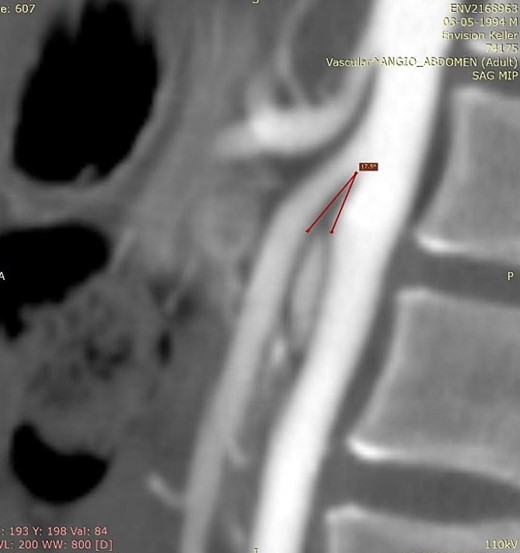

We present the case of a 21-year-old male patient, with a history of laparoscopic cholecystectomy and 3 cryoablations for Barret’s esophagus with grade III dysplasia, who presented with persistent postprandial vomiting that had caused weight loss of 11 kg in the last 2 years without apparent cause, associated with gastroesophageal reflux that has worsened over time, occasional stabbing abdominal pain in the epigastrium, painful constipation, bloody stools and steatorrhea, managed clinically and symptomatologically without improvement in the condition. On evaluation, the patient was thin, with a BMI of 17.31 kg/m2, and in paraclinics, in endoscopy (Figs 1 and 2), Barret’s esophagus and hiatal hernia; In tomography (Figs 3 and 4), an aortomesenteric angle of 17.5°, with aortomesenteric distance of 4 mm.

Computed tomography. Aortomesenteric distance of 4 mm. Wilkie’s syndrome.